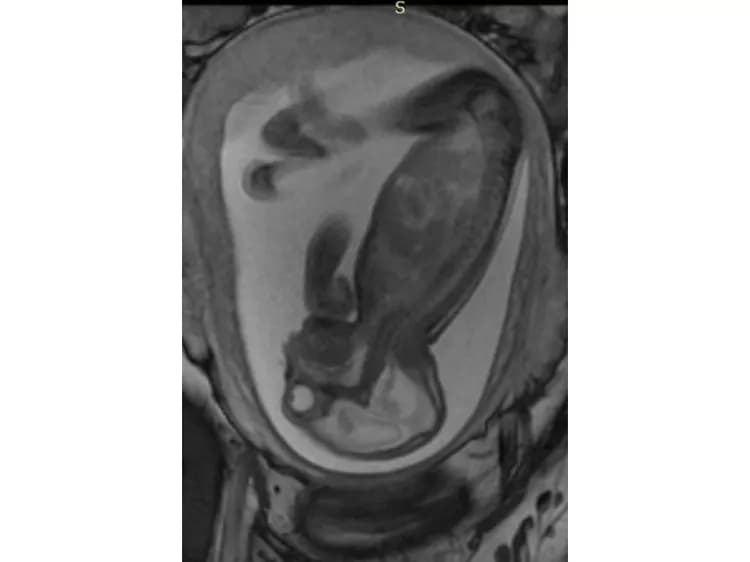

In a third study, ultrasound and fetal MRI were performed on pregnant patients with Zika virus infection at different gestational ages. Once the babies were born, they underwent ultrasound, CT and MRI. The researchers then created 3-D virtual and physical models of the skulls. More than half the babies had microcephaly, brain calcifications and loss of brain tissue volume, along with other structural changes.

"The emergence of Zika virus in the Americas has coincided with increased reports of babies born with microcephaly," said study author Heron Werner Jr., M.D., Ph.D., from the Department of Radiology at Clínica de Diagnóstico por Imagem. "An early diagnosis may help in treating these babies after birth. Moreover, the knowledge of abnormalities present in the central nervous system may give hints about the pathophysiology of the disease."